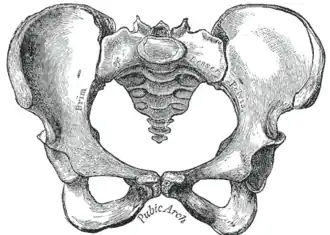

Skeletal structure frames the overall shape of the body and does not alter much after maturity. Males are, on average, taller, but body shape may be analyzed after normalizing with respect to height. The length of each bone is constant, but the joint angle will change as the bone moves.[7] The dynamics of biomechanical movement will be different depending on the pelvic morphology for the same principle. The fascia anatomy of the sides of the sacral diamond area, which regulates its shape and movement, corresponds to the fascial thickenings that are part of the sacral complex of the thoracambular fascia, which surrounds the sacroiliac joints both posteriorly and, from the iliolumbar ligaments, anteriorly. The biochemical properties of the muscular bands have repercussions from the inside to the outside and vice versa.[8] The shape of the posterior muscular and adipose tissues seems to correspond with the general pelvic morphology. The classification is as follows the gynecoid pelvis corresponds to a round buttocks shape, the platypelloid pelvis to a triangle shape, the anthropoid pelvis to a square shape and the android pelvis to a trapezoidal gluteus region.[8] The trapezoidal shape is what gives steatopygia its specific shape and appearance.

Female traits

Widening of the hip bones occurs as part of the female pubertal process,[9] and estrogens (the predominant sex hormones in females) cause a widening of the pelvis as a part of sexual differentiation. Hence females generally have wider hips, permitting childbirth. Because the female pelvis is flatter, more rounded and proportionally larger, the head of the fetus may pass during childbirth.[10] The sacrum in females is shorter and wider, and also directed more toward the rear (see image).[11] This sometimes affects their walking style, resulting in hip sway.[12] The upper limb in females have an outward angulation (carrying angle) at elbow level to accommodate the wider pelvis. After puberty, hips are generally wider than shoulders. However, not all females adhere to this stereotypical pattern of secondary sex characteristics.[13] Males and females generally have the same hormones, but blood concentrations and site sensitivity differs between males and females. Males produce primarily testosterone with small amounts of estrogen and progesterone, while women produce primarily estrogen and progesterone and small amounts of testosterone.[14]